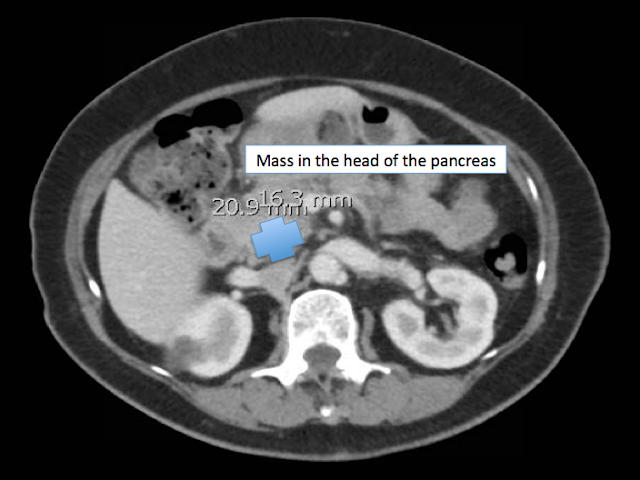

CT of the abdomen and pelvis revealed a mass within the pancreatic head and uncinate process, most likely representing pancreatic neoplasm. There was mass effect noted with resultant mild intrahepatic and extrahepatic biliary duct and pancreatic duct dilatation. Also evidence of pancreatitis likely secondary to pancreatic tumor.

A subsequent endoscopic retrograde cholangiopancreatography (ERCP) revealed a dilated common bile duct and pancreatic duct but no significant intrahepatic biliary dilation. With ultrasound a hypoechoic 24 X 23 mm mass was seen in the head of pancreas with upstream dilation of both ducts. Vessels looked clear of the mass. Small amount of ascites noted. Small peritumor lymph node seen.